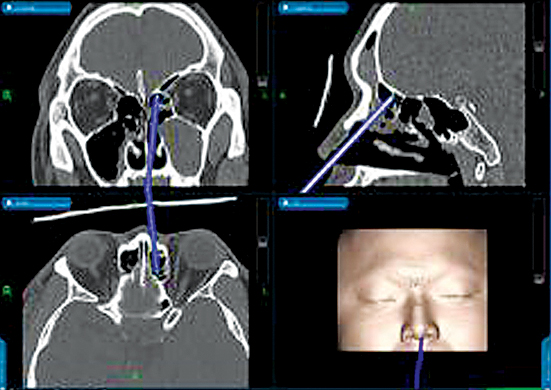

이 수술법은 수술 시야에 있는 탐침자(probe)의 위치가 수술 전 찍은 전산화단층촬영 영상에서 실시간으로 3차원적인 해부학적 정보를 제공해 수술 중에 병소의 정확한 위치 확인이 가능해지고, 정상 해부학적 구조물들이 소실되고 왜곡되더라도 합병증을 최소화하고 좀 더 완벽한 수술을 시행할 수 있도록 도와주어 부비동염 수술의 혁신적인 진화라고 의료계에선 판단하고 있다.

이 수술법은 수술 시야에 있는 탐침자(probe)의 위치가 수술 전 찍은 전산화단층촬영 영상에서 실시간으로 3차원적인 해부학적 정보를 제공해 수술 중에 병소의 정확한 위치 확인이 가능해지고, 정상 해부학적 구조물들이 소실되고 왜곡되더라도 합병증을 최소화하고 좀 더 완벽한 수술을 시행할 수 있도록 도와주어 부비동염 수술의 혁신적인 진화라고 의료계에선 판단하고 있다.